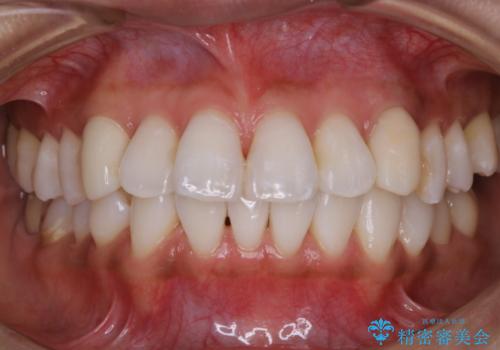

- インビザラインで矯正治療中にクリーニングを希望されました。PMTC60分コースで、クリーニングと歯ブラシ指導を行いました。

磨けているようでも、染出しをして目に見えるプラーク(歯垢)を確認することで、より正しいブラッシング方法を身につけることができます。インビザライン中は、歯にアタッチメントをつけるため、歯の表面がデコボコしてプラークが付きやすい状態になります。毎日のケアでしっかりと汚れを落として虫歯や歯周病・口臭のリスクを減らしていくことが大切です。定期的にメンテナンスを行い、ケアがどれくらい出来ているか確認したり歯科医院で専門的な機械や器具によるPMTCを行うことをおススメします。